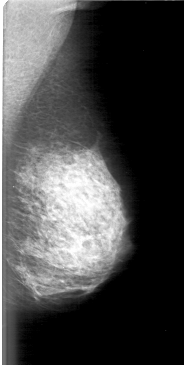

D_4079_1.LEFT_MLO

LEFT_MLO LINES 5101 PIXELS_PER_LINE 2566 BITS_PER_PIXEL 12 RESOLUTION 43.5 NON_OVERLAY